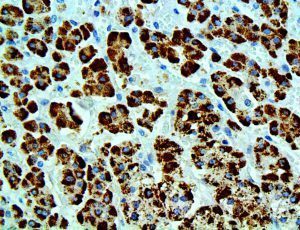

It is the ICU physician who is most likely to witness one of the deadliest manifestations of the abnormal immunological response, the cytokine storm syndrome (CSS). This response is also referred to by some as the cytokine release syndrome (CRS). CSS is characterized by continuous activation and expansion of macrophage and lymphocyte populations, which secrete large amounts of cytokines, causing the cytokine storm. This massive cytokine release is akin to hemophagocytic lymphohistiocytosis (HLH) disease, a syndrome characterized by initial unchecked and persistent activation of cytotoxic T lymphocytes and NK cells.

Clinical and laboratory manifestations of HLH include fever, enlarged liver and/or spleen, neurologic dysfunction, coagulopathy, liver dysfunction, cytopenias (i.e., low levels of erythrocytes, leukocytes, and/or platelets), hypertriglyceridemia, hyperferritinemia, hemophagocytosis, and eventually diminished NK cell activity as the immune system becomes progressively paralyzed. HLH can be familial (primary HLH) or secondary to another disease process (sHLH), such as rheumatic disease, in which it is referred to as macrophage activation syndrome (MAS, characterized by elevated ferritin).